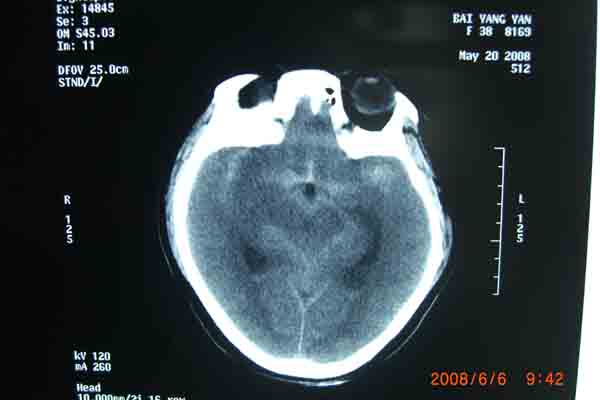

6月6日上午,在明州医院放射科的DSA检查室内。上海的神经外科专家及麻醉科在为一位38岁的云南来宁波打工中年女病人做颅内动脉瘤(眼颈交界处7*3.5cm)血管内栓塞手术。无影灯下,准备工作在有条不紊地进行着。全身麻醉后。介入手术开始了,手术医生以非常娴熟的手法,在右侧股动脉内置入导管,在显像下,随着导丝进入,顺利到达动脉瘤瘤腔内。随着弹簧圈进入,瘤腔内被充填。造影后,显示位置良好。所有的神经外科医生知道,在手术过程中,如果发生动脉瘤破裂,那后果不堪设想。手术成功了,大家悬着的心放下了。整个手术时间仅仅用了1个半小时。手术后,病人即清醒,送回病房。

回想这个病人是5月 20 日,因为在早晨起床后,突然昏迷不醒,跌到在地,被家人送往明州医院急症室,经过医生检查,这个病人已经瞳孔放大,呼吸停止。紧急地插入气管导管后,给予呼吸机使用。经过医院上海神经外科专家检查病人后,指出这是动脉瘤破裂出血导致的呼吸压制。需要头颅CT检查,在捏着皮球保持呼吸道通畅,即刻行头颅CT检查,确认为动脉瘤破裂出血,前交通动脉瘤破裂为主。专家看了片子后,认为如果行双侧脑室外引流,将血液引出,可能会使呼吸恢复。马上送手术室做急症手术,引流出血性脑脊液后,病人呼吸慢慢恢复了。经过3个星期的正规治疗(高血压,高颅压,高体温)(抗血管痉挛,抗感染)(外引流)病人终于度过了危险期。在6月6日上午成功进行了颅内动脉瘤血管内栓塞手术。